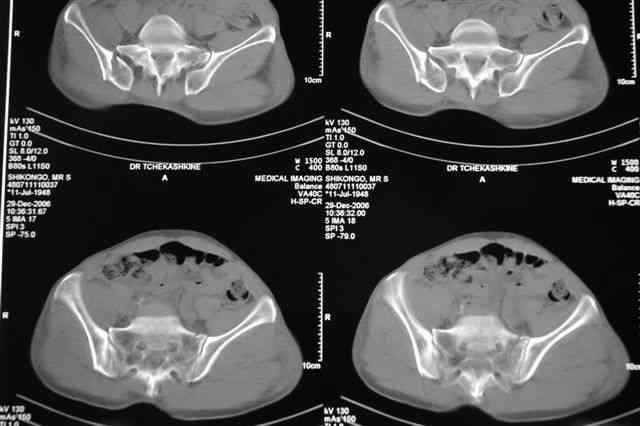

Djoldas Kuldjanov 08 Январь 2007, 17:50

Таз надо дообследовать, нужны Inlet and Outlet pelvic views, тогда будет точная картина и можно обоитись минимальным, только передним Ex-Fix, на наших предыдущих дисскуссиях я показывал, 5 мм Synthes Half Pins под CRM за Spina Iliaca Inferior место прикрепления прямой мышцы бедра в супраацетабулярной части.

Я помню технику транссакральной фиксации тазового кольца длинными 5 мм Шанцами - повреждения типа В, в этом же случае задний отдел тоже вовлечен

т.е комбинированная нестабильность, поэтому вопрос - достаточно ли только двух Шанцев для стабилизации таза? Что вы думаете об anterior Right SI joint plating + tension band plating from the back.?

PS после фиксации бедра под Эопом посмотрел инлет и аутлет проекции, насколько репонируемо смещение правой половины таза *невооруженными*

руками - никаких шансов улучшить позицию иначе бы конечно воспользовался длинными Шанцами сразу после бедра.